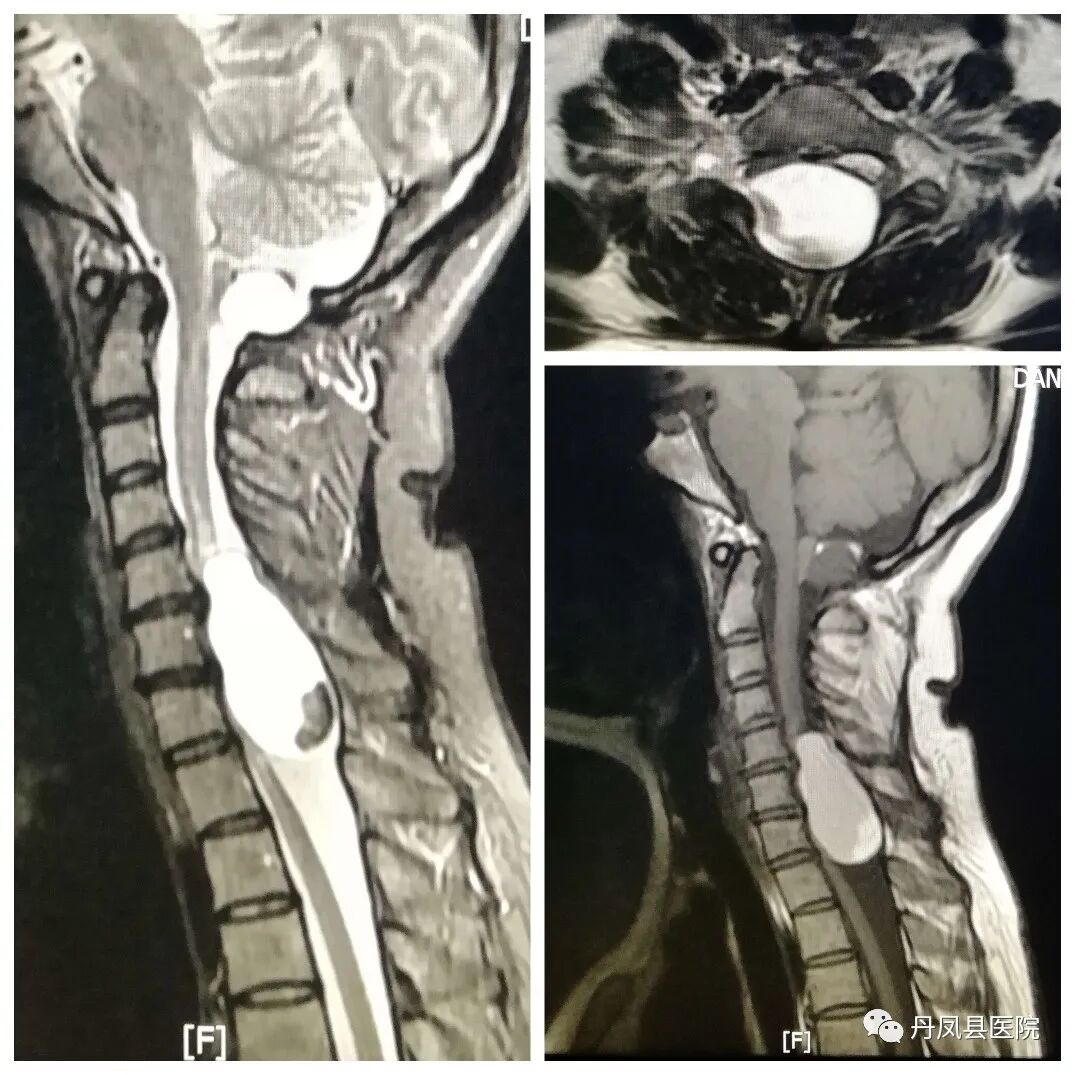

![椎管内囊肿.jpg]()

椎管内囊肿

![磁共振脊柱全场拼接.jpg]()

磁共振脊柱全长拼接